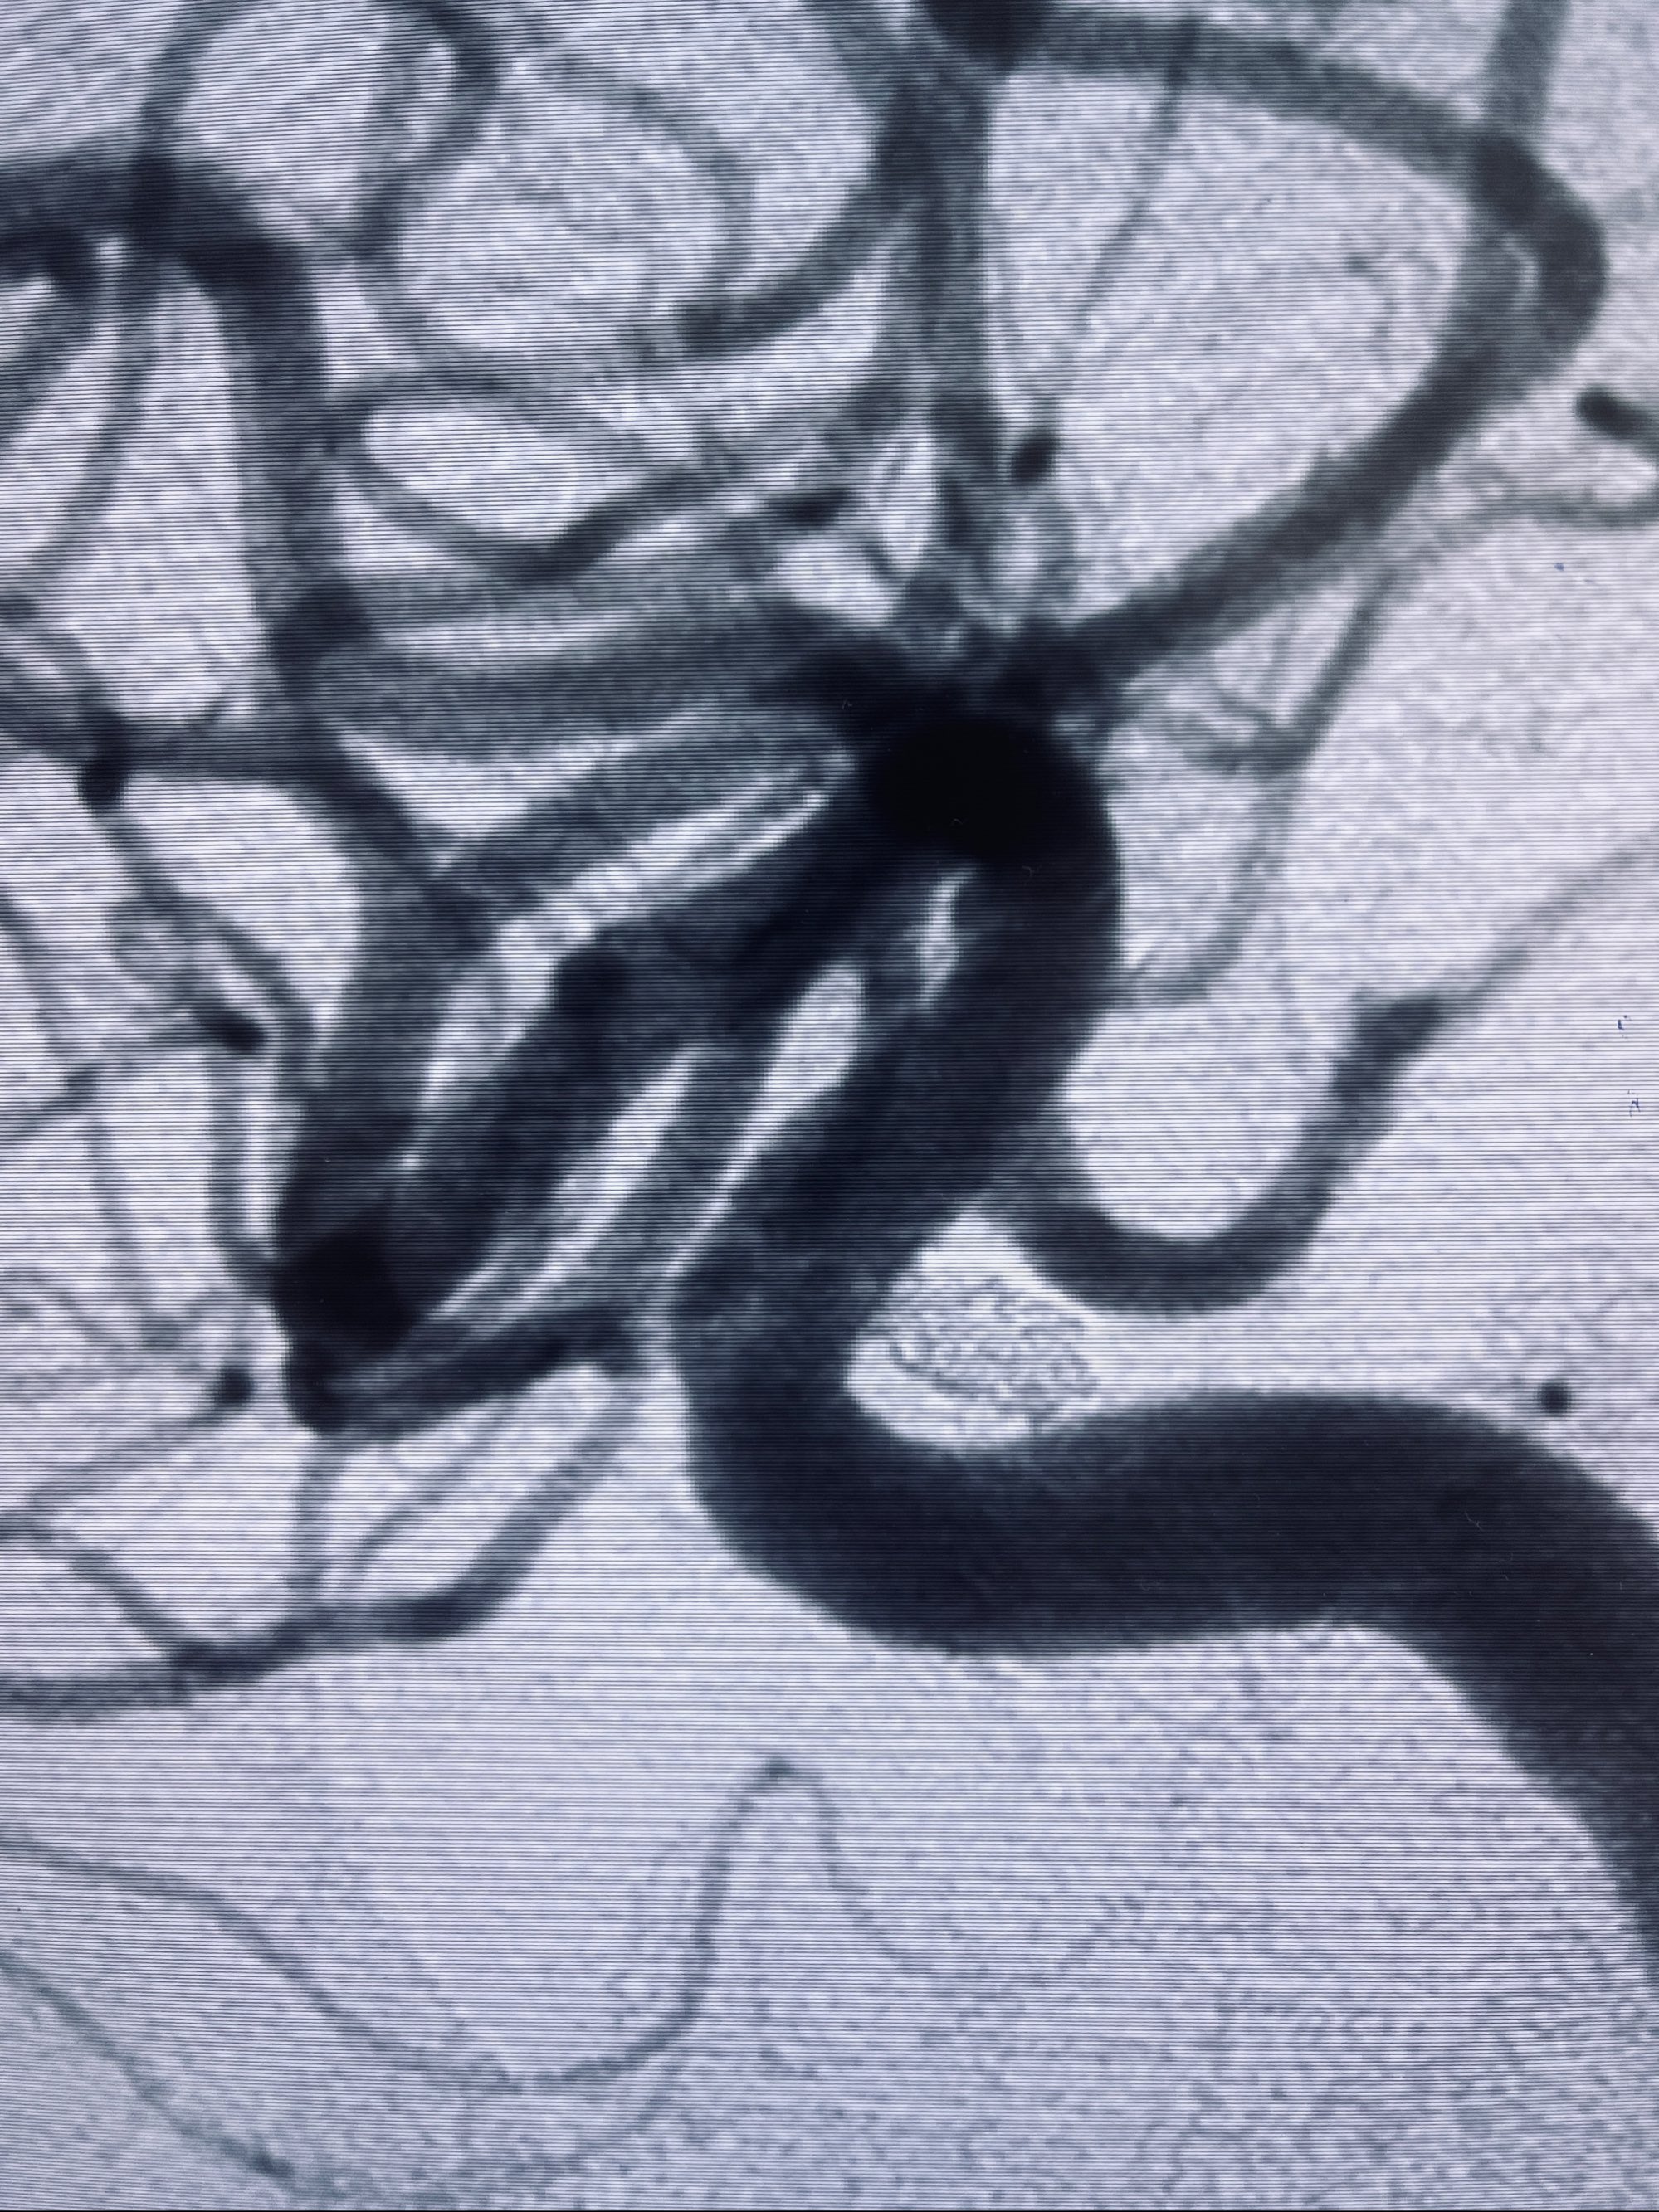

现病史:患者,女,因“左侧颈眼动脉瘤支架辅助栓塞术后1年余”入院。患者2021-5-24因“头晕”就诊于华山医院查头颅CTA、DSA诊断左侧颈眼动脉瘤,随后在全麻下行“左侧颈眼动脉瘤支架辅助栓塞术”,术顺,术后恢复可,予以阿司匹林、氯吡格雷抗血小板,阿托伐他汀钙片降脂稳定斑块。3月后华山医院复查脑血管造影动脉瘤未见明显复发或残留,停用降脂药物。目前患者无明显不适主诉,口服阿司匹林抗血小板治疗,为行脑血管造影收入我科。

1.左侧颈内动脉眼动脉段动脉瘤(支架辅助栓塞术后)

2022-09-29复查DSA